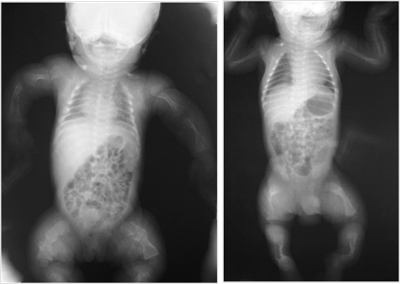

بیماری آکندروپلازیا (Achondroplasia) نوعی کوتاه قدی مادرزادی است که مشخصه آن کوتاه بودن طول اندام ها است. مشکل اصلی در این بیماران تبدیل غضروف به استخوان در صفحات رشد بخصوص در استخوان های بلند اندام ها است.

◊ قد کوتاه همراه با اندام های فوقانی و تحتانی کوتاه بخصوص کوتاهی در بازو و ران

اختلال تکوینی در آکندروپلازیا که شایع ترین علت کوتولگی در انسان است، نوعی اختلال اتوزومی غالب ناشی از جهش های اختصاصی در FGFR3 در ناحیه 4p16 می ­باشد. %98 این بیماران دارای یک جایگزینی انتقالی G به A و حدود 1% جایگزینی متقاطع G به C در نوکلئوتید 1138 می ­باشد. این دو موتاسیون موجب قرارگیری اسیدآمینه آرژنین به جای اسید آمینه گلیسین در کدون 380 در دومین ترانسمبرانس پروتئین FGFR3 می ­گردد.

ο هرچند در اواخر بارداري با تجزيه و تحليل عكس اسكلت جنين مي‌توان تشخيص داد.